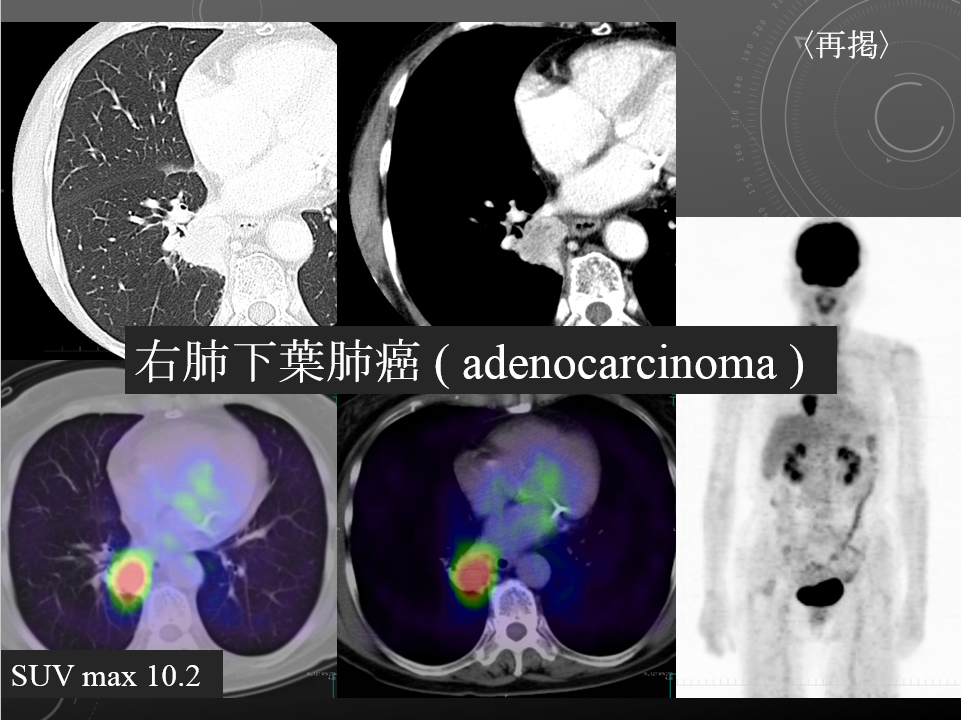

68F CEA 高値精査。消化器内科依頼。既往に脳梗塞、心筋梗塞、胃ポリープあり。

右肺下葉腺癌。

右肺下葉の縦隔側には最大径31mm大の不整形な腫瘤性病変を認めます。表面には部分的にspicula所見が見られ、胸膜に広汎に隣接するように存在しています。内部は辺縁を中心に淡い造影効果を呈しています。原発性肺癌病巣が疑われます。肺門部にはリンパ節腫大像が見られますが、縦隔領域に明らかに有意なリンパ節腫大は指摘出来ません。

左肺下葉に末梢側には淡い濃度上昇所見が見られ、GGO病変が疑われます。この他、肺野に明らかな腫瘤性病変は指摘できません。

・Lung cancer s/o

SUVmaxは10.2

右肺下葉内側の腫瘤に一致して異常集積を認める。

右肺下葉原発性肺癌 ( adenocarcinoma )

右肺下葉原発性肺癌 ( adenocarcinoma )